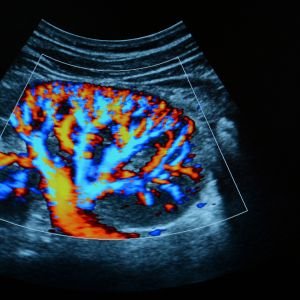

Color & Fetal Doppler

Color & Fetal Doppler in Saharsa - Sparssh Imaging & Diagnostics

At Sparssh Imaging & Diagnostics, we provide advanced Color Doppler and Fetal Doppler ultrasound services in Saharsa. These techniques help in assessing blood flow, monitoring fetal health, and detecting any abnormalities in pregnancy. Our experienced team, led by Dr. Ankur Chand, ensures accurate, real-time results to provide optimal care for both mother and child.

Precise Blood Flow Measurement

These tests provide precise information about blood flow, which is vital for monitoring pregnancy and detecting potential complications.